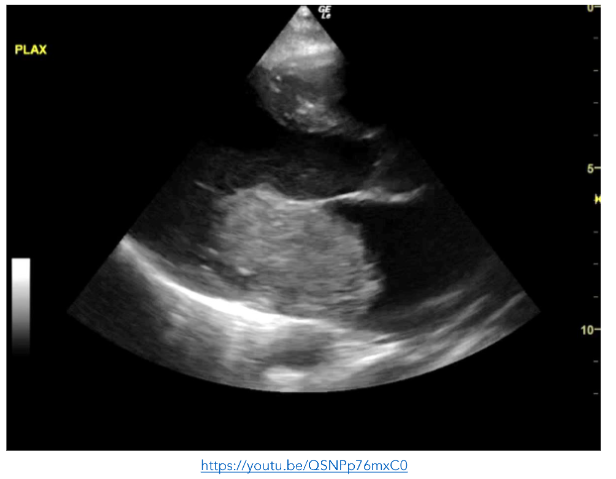

The boy was re-examined by a senior clinician following the initial survey and was noted to have a grade 3/6 ejection systolic murmur. Point of care echocardiogram was performed revealing a very large gelatinous mass occupying >50% of the left atrium.

While in ED he developed a work of breathing and became hypoxic. Point of care echocardiography was repeated and showed a distended and plethoric IVC, with innumerable B-lines anteriorly.

His symptoms rapidly resolved with a stat dose of intravenous furosemide. On transfer to PICU, he became hypotensive secondary to cardiac obstruction. Due to his clinical instability, he proceeded to theatre where he underwent resection of a cardiac myxoma, the mass initially identified on POCE in the ED. Use of POCE rapidly clarified the broader issues in this critically unwell patient with a relatively rare presentation for his age-group, additionally it guided his resuscitation and onward care accurately.

Figure 9: PLAX view showing a very large gelatinous mass occupying >50% of the left atrium